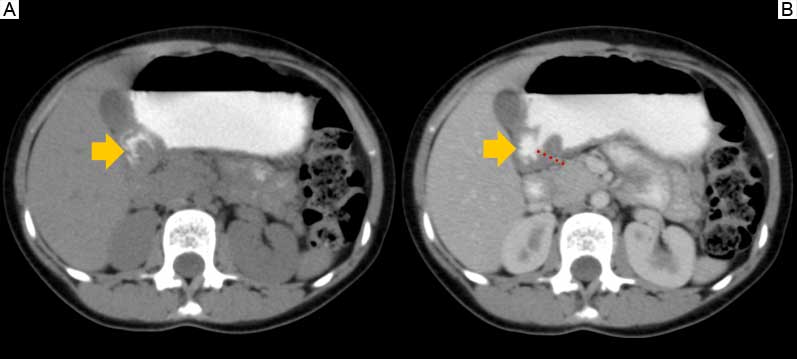

Tomografía abdominopélvica simple y contrastada: estómago distendido con presencia de contraste en su interior, a nivel antro-pilórico, engrosamiento de la pared con paso filiforme del contraste hacia el duodeno, vesícula biliar moderadamente distendida, hipodensa, pared delgada; resto de las estructuras sin alteraciones (figura 4).

Botello et al., reportaron una reseña de un paciente de sexo masculino, de 57 años de edad, con antecedente de dolor abdominal en epigastrio, acompañado de náuseas y vómito, descubriendo en el examen tomográfico engrosamiento antro-pilórico y bulbo duodenal compatibles con signos típicos de páncreas anular.13 En la paciente se encontró engrosamiento antro-pilórico en el estudio tomográfico, relacionado con páncreas anular descrito en la literatura. El estándar de oro para diagnosticar páncreas anular es la exploración quirúrgica completa del duodeno y la cabeza del páncreas.14 El tratamiento definitivo es la revascularización quirúrgica del sitio del anillo pancreático (duodenoyeyunoanastomosis). No obstante, el procedimiento tiene una alta tasa de complicaciones quirúrgicas como la formación de fístula, pancreatitis, laceración pancreática o estenosis duodenal recurrente secundaria a la fibrosis local,15 es por ello que, hasta el momento, la paciente continúa en vigilancia por consulta externa en estrecho seguimiento sin haber sido explorada quirúrgicamente.